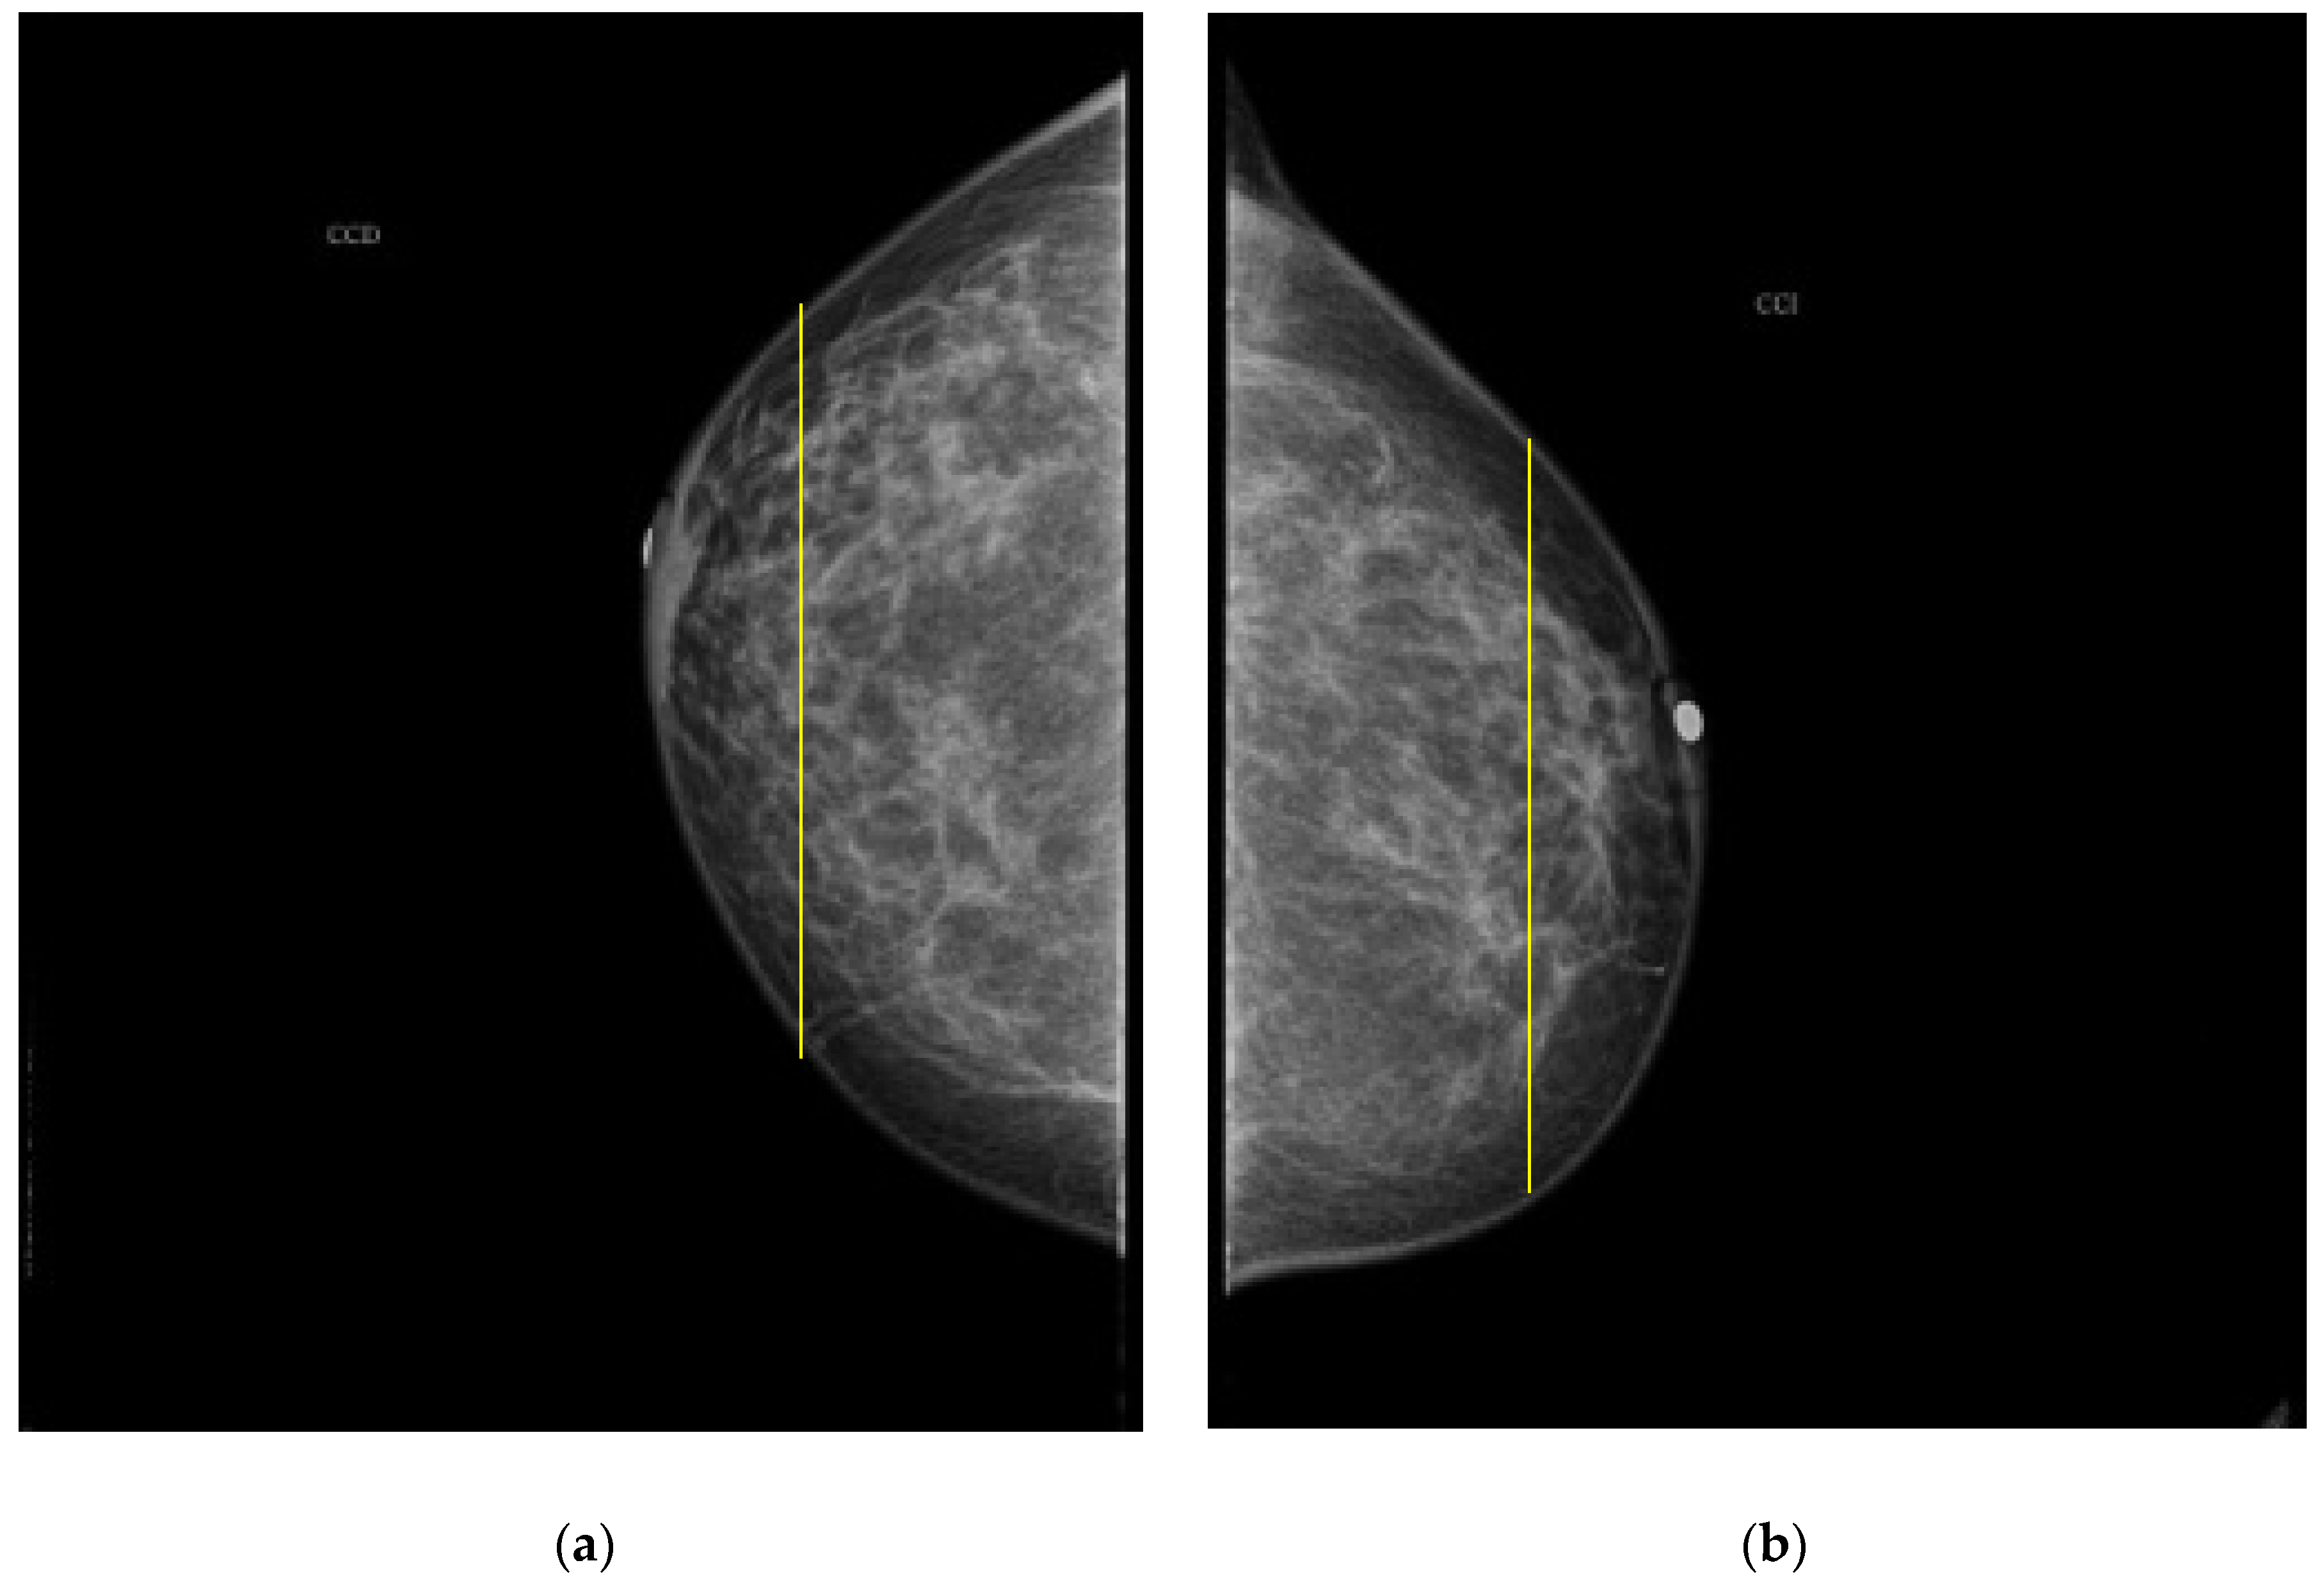

As it is noted, the same BI-RADS PBD for both breasts in all the participants was obtained by the specialist; meanwhile, a 61.5% was achieved by the described ATC clustering. An important uncertainty factor to be considered is that the electrodes ring position in most of the cases is not exactly the same on both breasts for each participant. As a consequence, different bioimpedance values are measured because the breast tissue distribution is not the same. For instance, the specialist evaluation for both breasts in participant 9 is BI-RADS c, while the described ATC classification resulted in BI-RADS b-c and c for the right and left breast, respectively. Such difference may be explained by analyzing the relative electrode ring positions on both breasts. The CC mammogram images of both breasts are shown in Figure 6, where the electrodes ring position is illustrated with a yellow vertical line. As it is observed, the left breast has less adipose tissue than the right breast. This amount of fatty tissue is the reason why a higher bioimpedance value is measured.

Figure 6. CC mammogram images of participant 9 and relative electrode ring position (yellow vertical line): (a) right breast; (b) left breast.